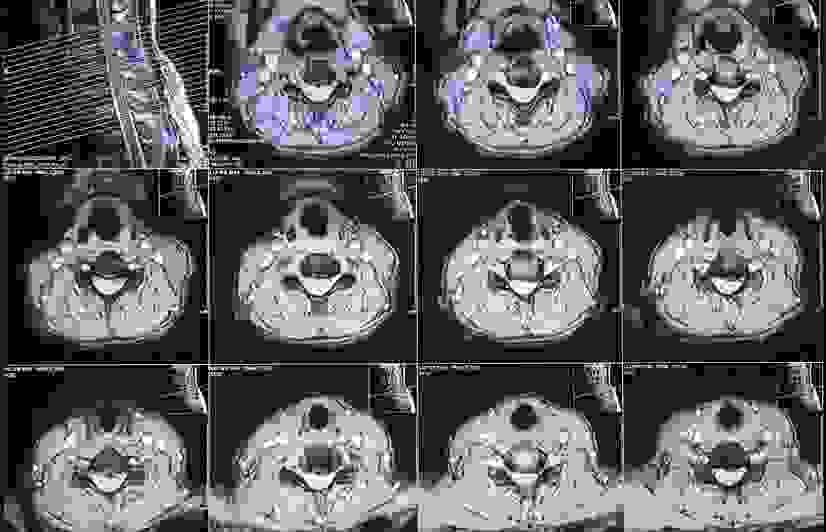

Phục hồi sau thoái hóa đốt sống cổ

Sau 10 ngày điều trị cho ổn định sức khỏe và giảm tình trạng phù nề, bệnh nhân được chỉ định phẫu thuật lấy đĩa đệm, hàn xương liên thân đốt cổ lối trước (ACDF)